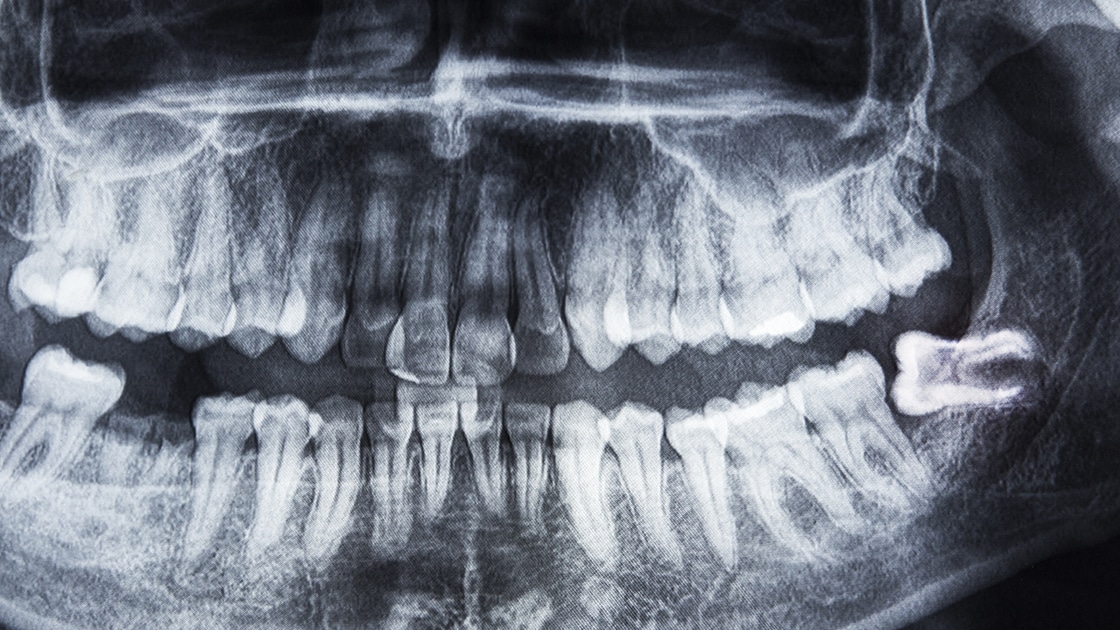

Endodontics Wisdom Teeth . Our compassionate team ensures a relaxed. They usually appear between the ages of. — wisdom teeth are the final molars located at the back of the mouth. — wisdom teeth are our third and last set of molars, which are the big chewing teeth right at the back of your mouth. — endodontists have specialized expertise. — wisdom tooth extraction is a common reason to visit an endodontist, especially for younger patients. — root canal therapy focuses on preserving a natural tooth by treating infection or damage within the tooth’s pulp chamber, while wisdom. By limiting their practice to endodontics, endodontists focus. — an endodontist is a dental specialist who focuses on complex tooth problems that primarily affect tooth pulp. They get their name because they typically emerge when you become an adult, and.